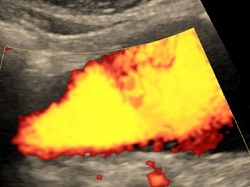

Zwężenie tętnicy biodrowej.